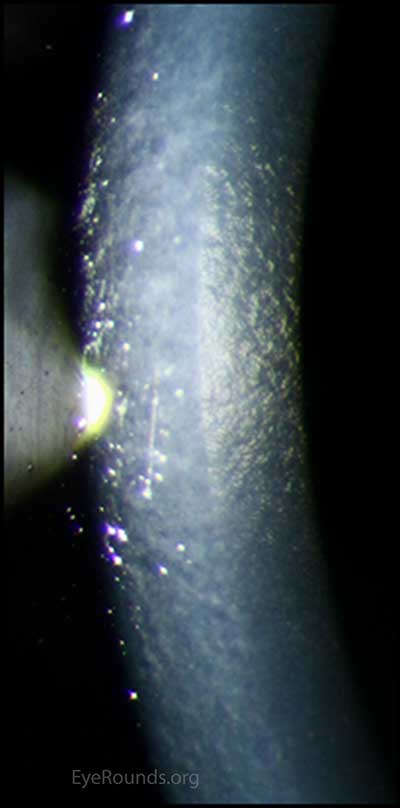

이경우에도 각막부종이 발생한 그부위를 확대해서 관찰하면

ICE syndrome 에서 나타나는 특징적인 ICE cell 의 모습을 관찰할수 있습니다.